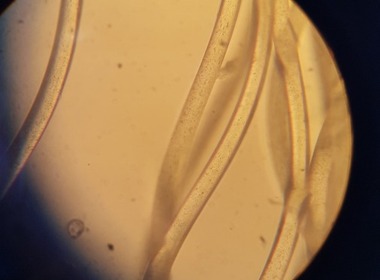

Kemijska popoldneva malo drugače sreda, 18.5.2022